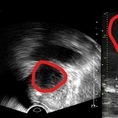

분당서울대병원 비뇨의학과는 기존 초음파보다 3배 더 높은 해상도의 실시간 영상을 통해 전립선 종양 평가가 가능한 마이크로 초음파 장비를 국내 최초로 도입했다고 밝혔다. 29MHz 마이크로 초음파를 사용하는 이 장비는 전립선과 주변의 해부학적 구조를 선명히 표시하고 표적 조직검사를 유도한다. 의심 영역을 실시간으로 확인하면서 전립선 조직의 미세한 변화와 병변을 식별하고 조직검사 채취를 위한 바늘을 정확한 위치에 삽입할 수 있다는 장점이 있다. ▲기존 전립선 초음파 사진(좌) 및 마이크로 초음파 사진(우). 기존 초음파는 전립선 부위(동그라미 친 부분)의 음영 차이로만 병변을 확인했지만, 마이크로 초음파는 높은 해상도를 통해 종양과 주변 조직의 모양까지 확인할 수 있다. 또한, 전립선 암 진단을 위한 초음파 검사 가이드인 PRI-MUS(Prostate Risk Identification Using Micro-Ultrasound) 위험도 식별 시스템과 연계돼있어 전립선암 병변의 악성 가능성 평가는 물론, 어느 부분에서 조직을 채취해야 하는지 정확히 판단할 수 있게 한다. PRI-MUS는 초음파 상 병변의 모양이나 크기를 자동으로 판단해 병변의 악성도를 1~5단계(